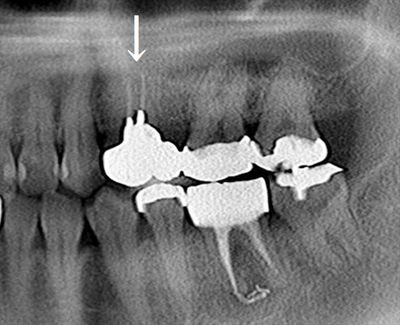

初診時のレントゲン写真です。

左上5(=第二小臼歯)が欠損しており、両サイドの歯に橋渡しするようにブリッジが装着されています。

左上④5⑥ブリッジ(左上4(=第一小臼歯)と左上6(=第一大臼歯)を支えとしたブリッジ)を

切断して、本日は左上4のメタルクラウンとメタルコアを除去します。(矢印)

二股に分かれた長いメタルコアがセットされています。